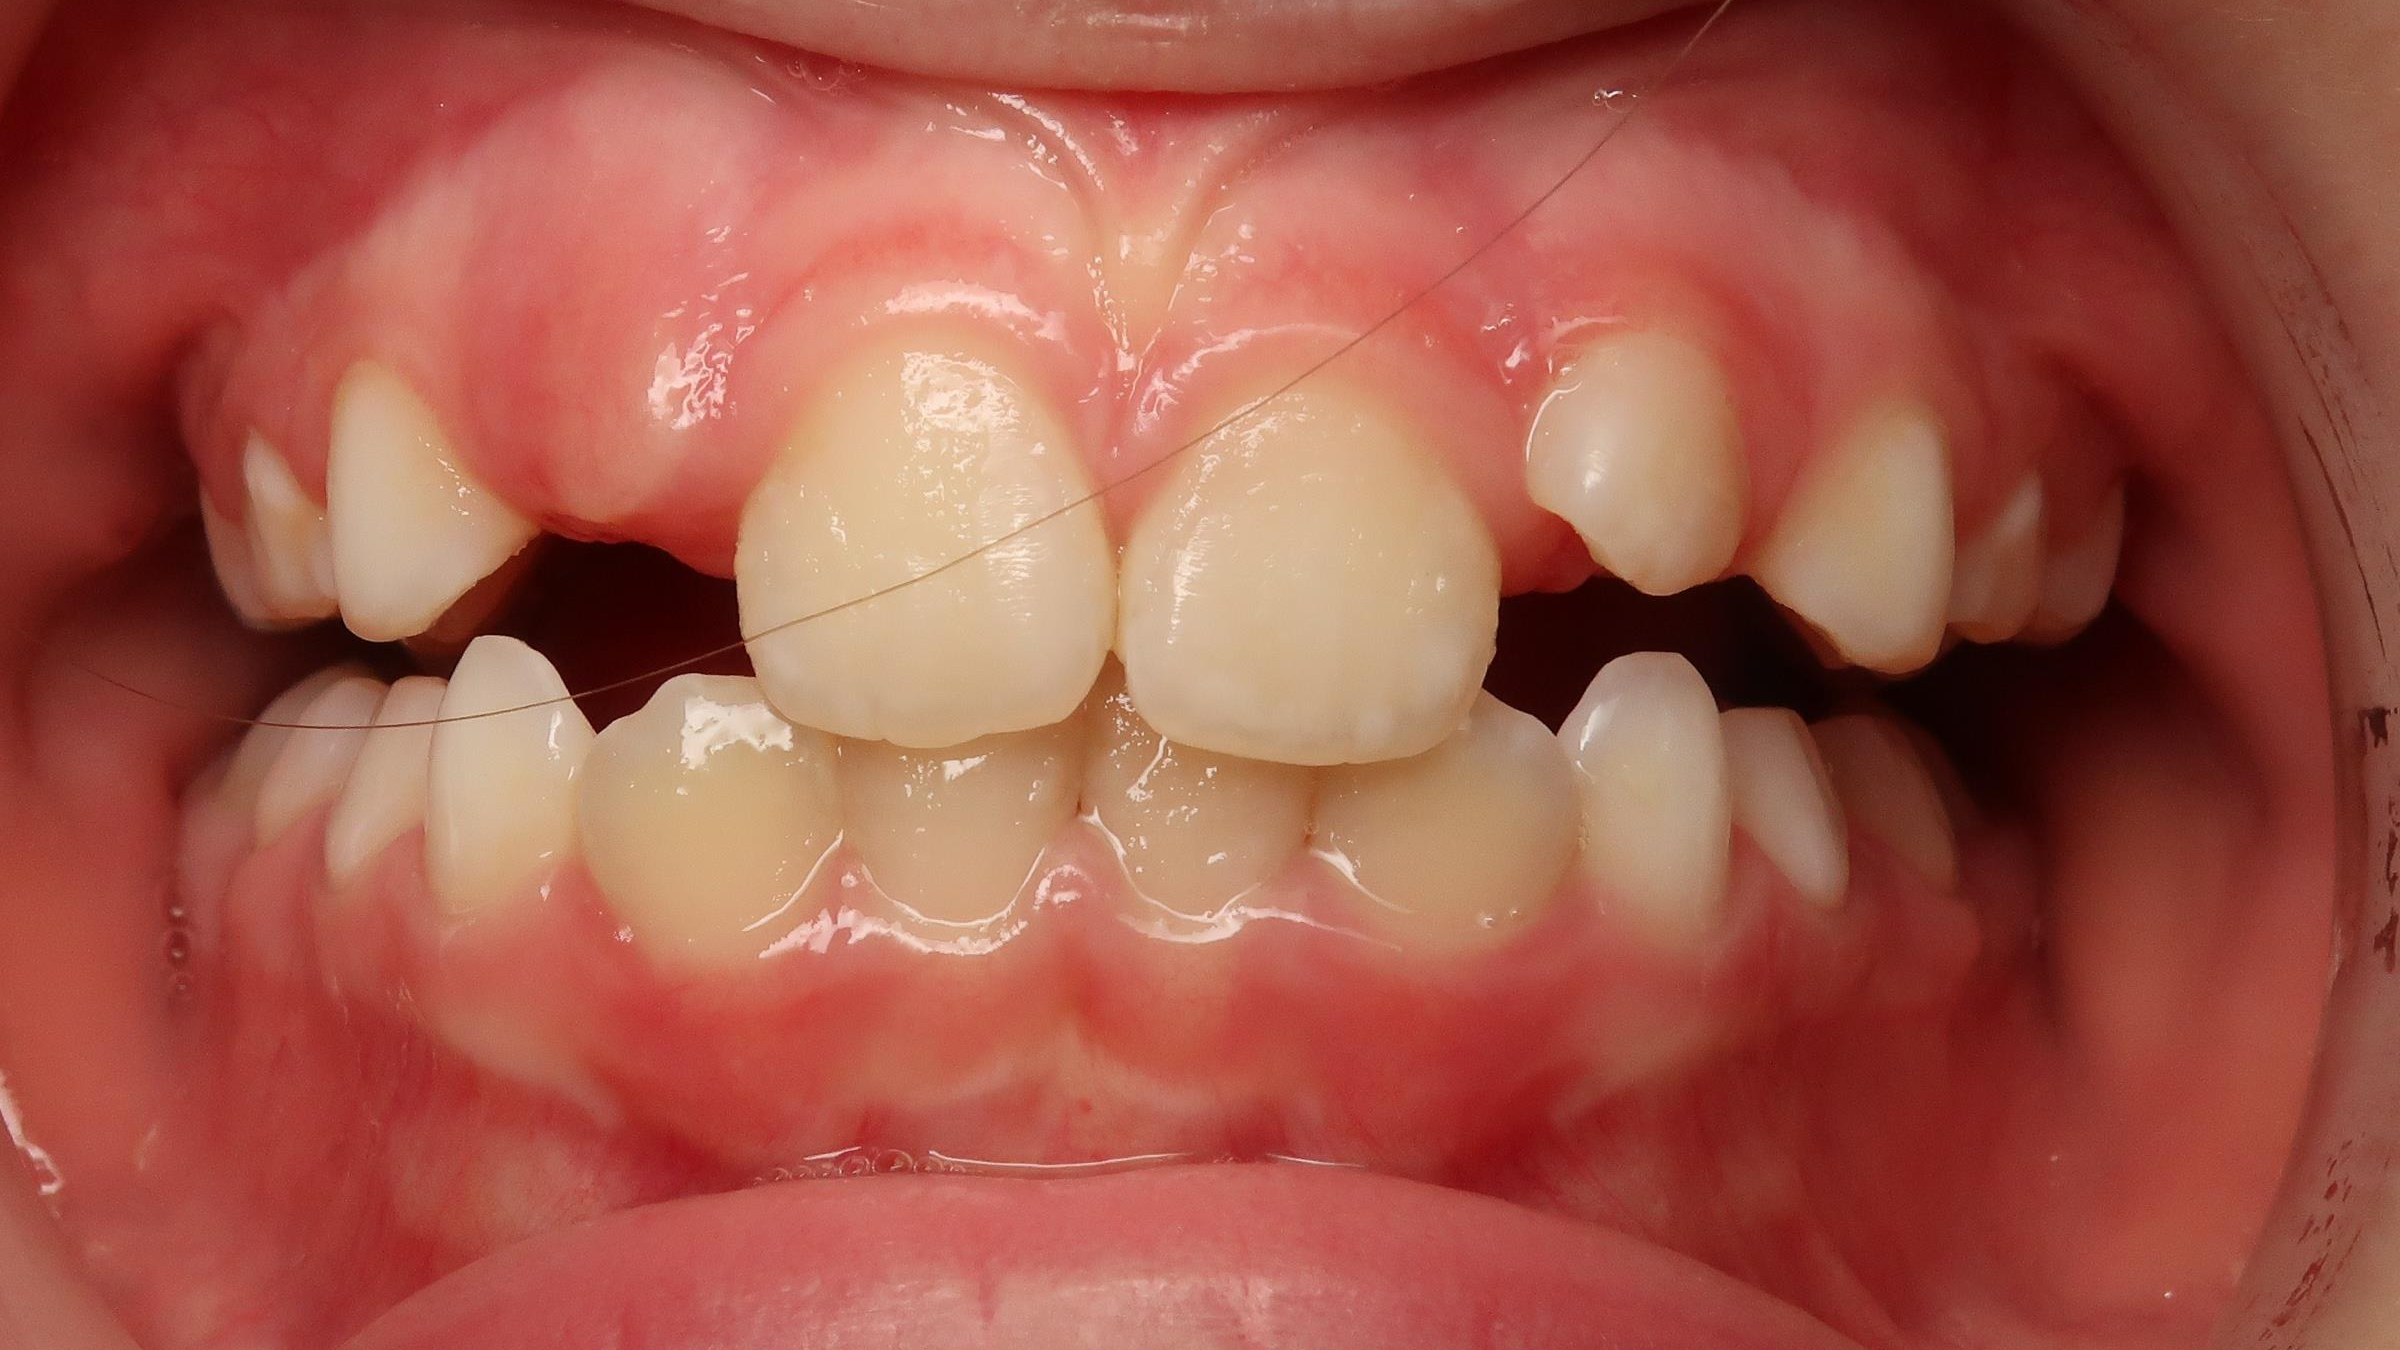

appareillage mobile pendant 13 mois

surveillance de la dentition pendant 16 mois

sectionnel multibagues pendant 24 mois

bilan début et en cours de traitement